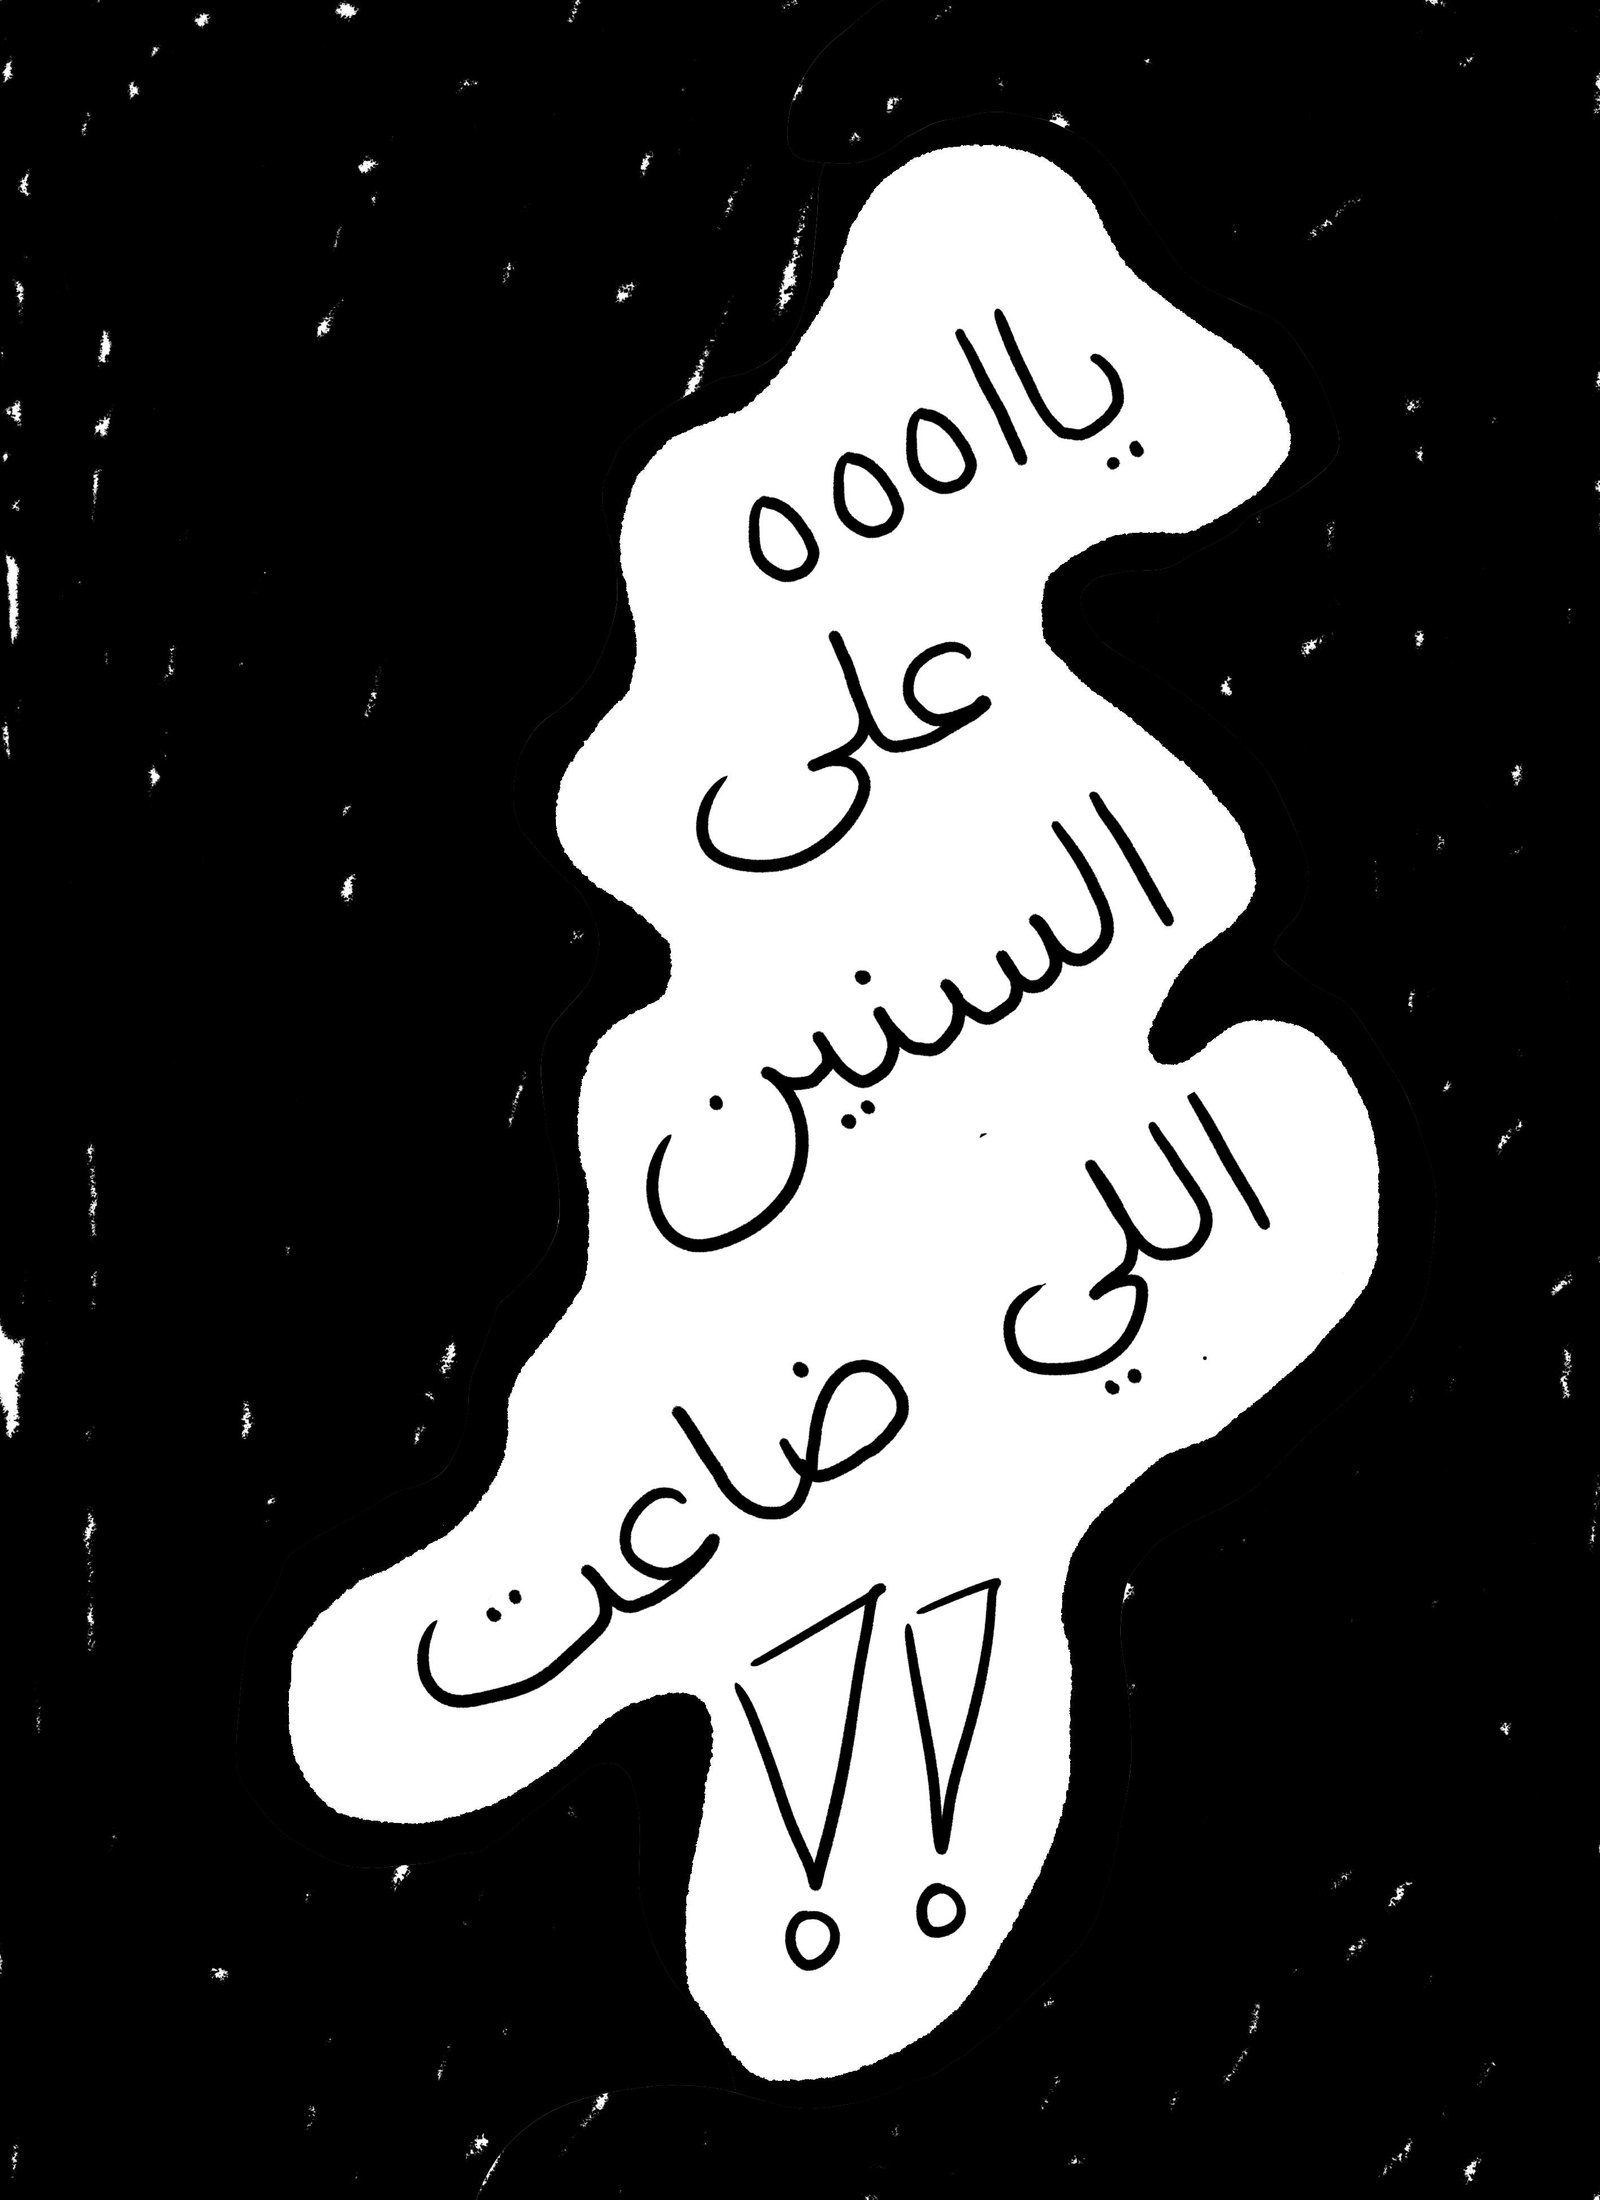

Blue Filter - first

The P.O.V of the female patient, the reality of what is happening.

We believe you